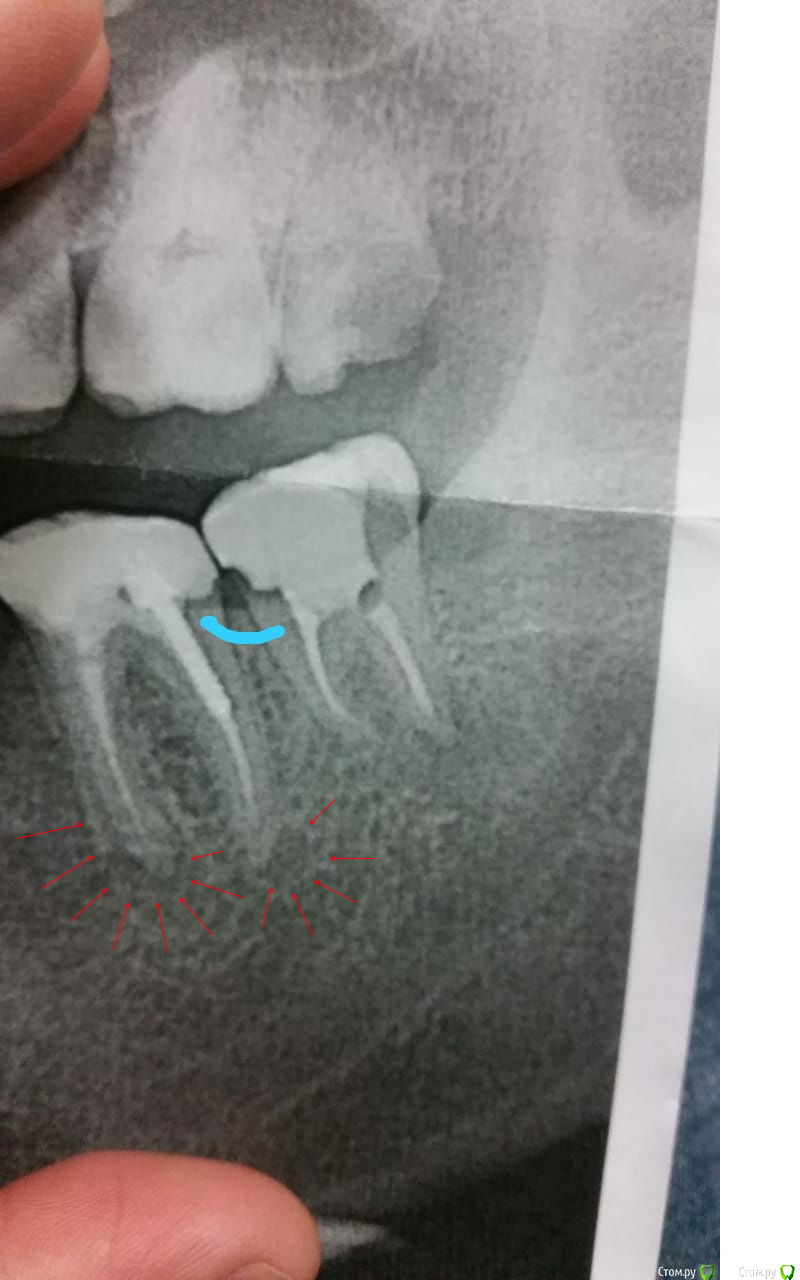

John_P Опубликовано 13 ноября, 2018 Поделиться Опубликовано 13 ноября, 2018 (изменено) Здравствуйте! Подскажите что делать. Пару недель назад сделали два зуба нижних (17-18) и удалили восьмерку верхнюю (16). Начал болеть сильно 18-й запломбированный зуб, хотя в нем нервы удалены. Болит когда по нему стучишь или ешь им. Пришел к врачу на прием, сказала что это пища забивается между зубов, нужно чистить ниткой и полоскать содой и что болит это десна а не зуб. Сделал снимок в другой клиники и врач сказал что зуб сделан не совсем правильно и его надо переделывать, потому что есть между зубов выпуклость где постоянно будет забиваться еда и вода и он скоро испортиться. И еще не понятно что со вторым корнем, который не просвечивается рентгеном. Снимок в приложении. Зуб болит дело в нем или нет не пойму. Подскажите что делать? Изменено 13 ноября, 2018 пользователем John_P Ссылка на комментарий

kramer Опубликовано 13 ноября, 2018 Поделиться Опубликовано 13 ноября, 2018 (изменено) Вы случайно не из США? В зубе 37 воспалительные очаги у корней, которые и дают боль. Либо перелечивать каналы в зубе, либо удалять зуб Изменено 13 ноября, 2018 пользователем kramer Ссылка на комментарий